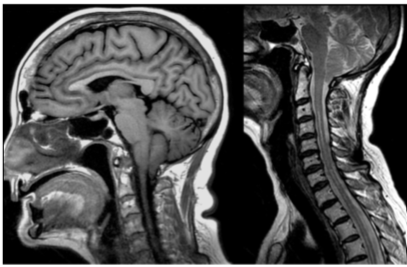

Paciente do sexo feminino, de 63 anos, realiza estudo por ressonância magnética para avaliação de cefaleia, sendo diagnosticado malformação de Chiari tipo I.

A respeito das características da malformação de Chiari tipo I tem-se que: